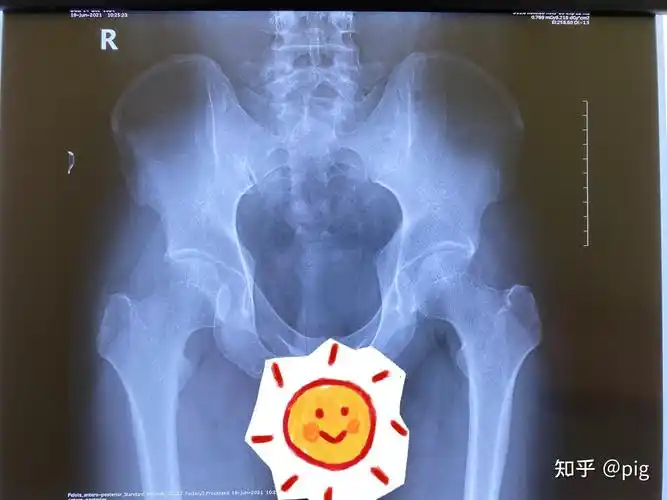

宝宝髋关节发育不良,致残率高!

发育性髋关节发育不良并髋关节骨性关节炎典型病例

先天性髋关节发育不良71拜托拜托求解答

先天型髋关节发育不良